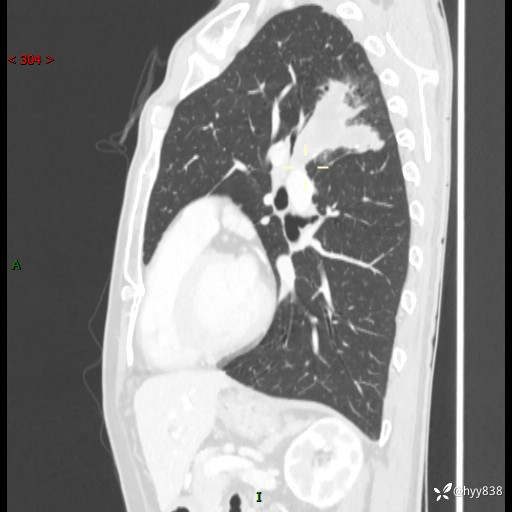

现病史:患者余4月前发现咳嗽咳痰伴痰中带血,无胸闷、胸痛、头晕、恶心、呕吐等不适,2天前因体检发现肺部结节遂于当地市第一人民医院行胸部CT薄层平扫+三维重建示:1.左肺上叶尖后段占位性病变考虑肿瘤性病变伴阻塞性肺炎,右肺上叶后段磨玻璃结节。2.肝内多发囊性灶、左肾结石。现患者为求进一步治疗,于我院门诊就诊,门诊以“肺结节”收入院。 自患病以来,精神、饮食、睡眠尚可,大小便正常,体力体重无明显减轻。

胸部CT增强扫描(外院平扫)